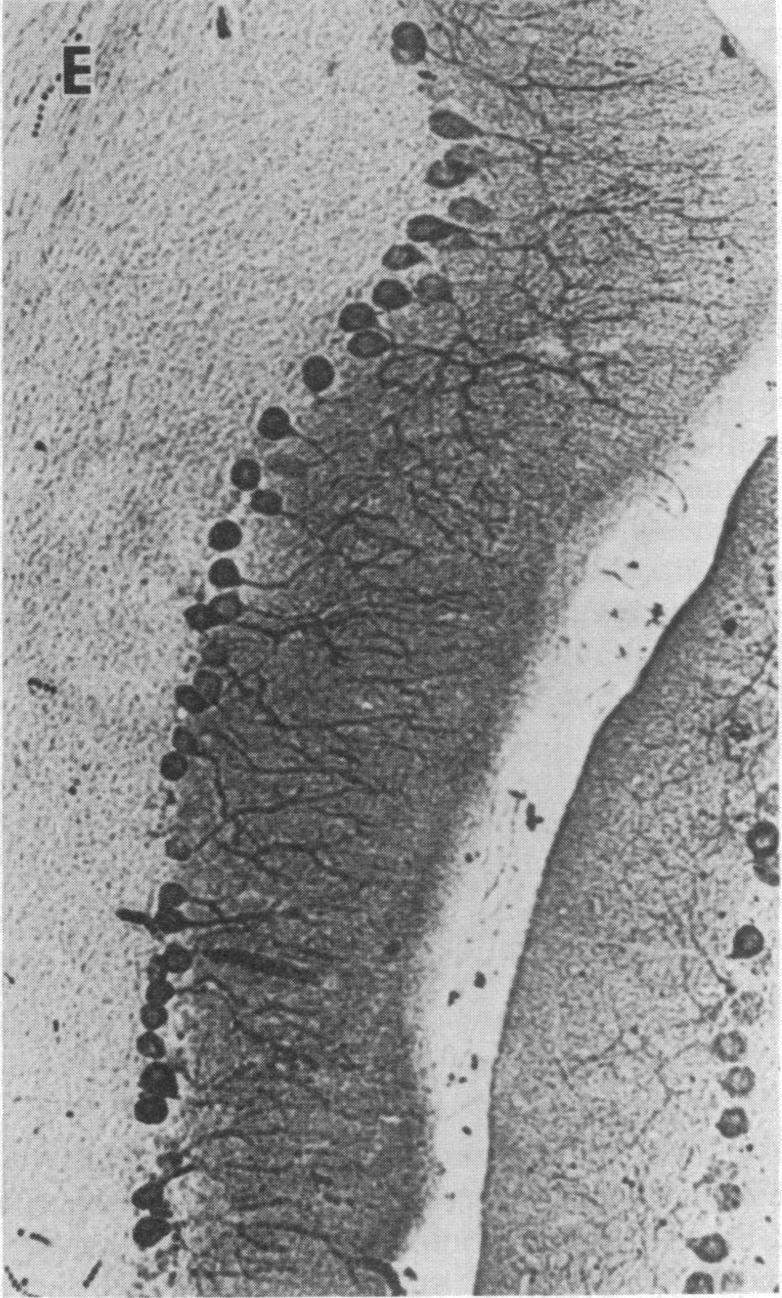

The cerebellum-specific hexadecapeptide cerebellin has been localized by immunocytochemical means to the perikarya and dendrites of cerebellar Purkinje cells. Biochemical analysis using ion-pairing HPLC shows cerebellin to first appear 5 days after birth, whereafter levels rise to a maximum at 25 days postpartum, and then decline to stable adult values. This same pattern of development occurs with a lag of approximately 5 days for the major metabolite of cerebellin, des-Ser1-cerebellin. The immunocytochemical picture of cerebellin in developing Purkinje cells mirrors the biochemical data. These results show that cerebellins represent unique quantifiable markers for the investigation of Purkinje cell maturation and lend support to the feasibility of using unique endogenous peptides to chart neurodevelopment.

小脑特异性十六肽小脑素已通过免疫细胞化学方法定位到小脑浦肯野细胞的胞体和树突。使用离子对高效液相色谱法进行的生化分析表明,小脑素在出生后5天首次出现,此后水平在产后25天升至最高,然后降至稳定的成年值。小脑素的主要代谢产物去丝氨酸1-小脑素的发育模式相同,但滞后约5天。发育中的浦肯野细胞中小脑素的免疫细胞化学图像与生化数据相符。这些结果表明,小脑素是研究浦肯野细胞成熟的独特可量化标志物,并支持使用独特的内源性肽来描绘神经发育的可行性。